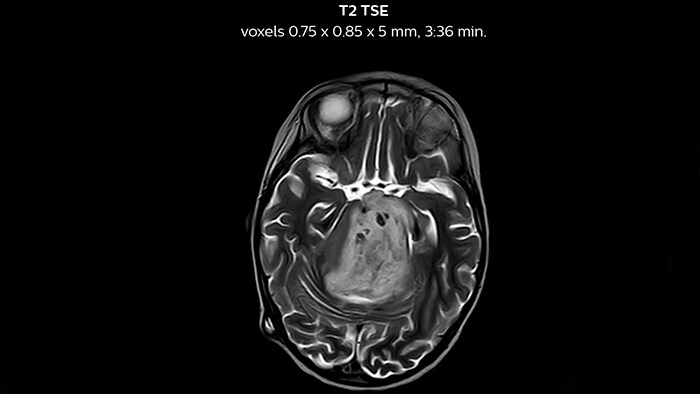

“We have been very, very pleasantly surprised by the quality of the images,” says Dr. Mahajan. “I have shown Prodiva images to people around the world during my travels.” Ingenia Prodiva 1.5T includes such features as dStream digital broadband technology to increase image quality with high SNR. “The system came with its newest sequences that allow us to perform advanced techniques like excellent diffusion in the brain and other body parts as well, spectroscopy, detailed neurography, CSF flow studies, imaging of difficult areas like skull base, tractography, DTI, and even DTI of the spinal cord – all of this is available to us.” The radiologists at Mahajan Imaging were also impressed by the quality of cardiac MRI. “We have done some MR angiography of the coronary arteries with the Prodiva and it provided excellent coronaries – and this was without using any contrast agent. We can also perform fantastic ngiography of other body parts.” “With Prodiva 1.5T, the images are very crisp and sharp, and the resolution is very good,” says Dr. Mahajan. “Imaging can be done in short scan times with excellent quality and broad range of possible applications, whether it is angiography, a scan with 3D reconstruction, any kind of more special images, what we do, the sharpness, resolution and the ease of use – everything counts in total when we are reporting.”